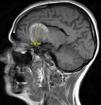

Más datosA 49-year-old woman suffered a first seizure episode. The brain CT scan (Fig. 1) revealed a giant aneurysm of the left internal carotid artery (ICA) with subtotal thrombosis (no CT-angio contrast uptake). Arteriography was decided (Fig. 2), showing a large left carotid-ophthalmic aneurysm, with a minimum patent portion (8 × 5 mm). The rest proved thrombotic. During arteriography, the patient developed hemiparesis and deviation of the vocal commissure, with arteriographic vasospasm that subsided with verapamil. Magnetic resonance imaging (Fig. 3) described the aneurysm with a left frontal parasellar location, measuring 4.2 × 3.9 × 3.6 cm, originating at the top of the left ICA and exerting a mass effect upon both anterior cerebral arteries and the left middle cerebral artery, as well as compression and right displacement of both frontal horns. The MR-angio study evidenced a 9-mm saccular dilatation in the supraclinoid portion of the left ICA, located within the lower third of the described lesion. A differential diagnosis with contained rupture of the aneurysm was considered. Surgery with clipping of the aneurysm was decided, with confirmation of its partial thrombosis and an intact capsule. The patient subsequently remained symptoms-free, with salt-wasting syndrome as the only posterior complication.